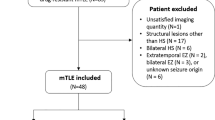

Retrospective data were collected from patients who were admitted to the Comprehensive Epilepsy Program Video EEG Monitoring (VEM) Unit at Royal Melbourne Hospital between 2004 and 2014. Inclusion criteria were patients with chronic drug resistant TLE that had undergone two [18F]-FDG scans and at least one epilepsy protocol MRI as part of their evaluation for potential epilepsy surgery. Localisation of the epileptogenic zone was determined in accordance with International League Against Epilepsy guidelines by the consensus of the consultant epileptologists on the basis of the ictal and interictal VEM findings, unequivocal patient history, and without any psychogenic events captured (Nightscales et al., 2020). In cases of bilateral TLE the hemisphere with the greater proportion of seizures was considered ipsilateral. The study was approved by the Melbourne Health Human Ethics Research Committee (QA2012044).